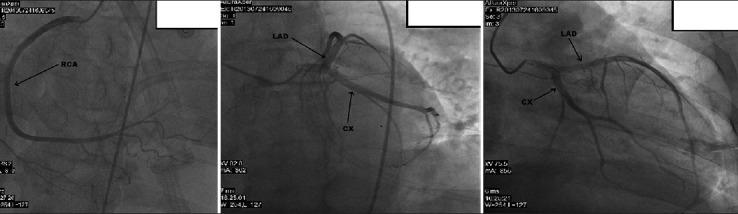

Chronic aortocaval fistula (ACP) is a rare complication of penetrating trauma to the abdomen. We report a case of traumatic ACP presenting with pulmonary hypertension and right heart failure symptoms 15 years after the initial penetrating injury. Although symptoms of pulmonary hypertension started 5 years ago, it was wrongly diagnosed and treated as chronic obstructive pulmonary disease. The presence of a continuous abdominal bruit and history of penetrating abdominal trauma gave rise to suspicion of a fistula, which was confirmed by computed tomography and angiography. Percutaneous closure of ACP was planned, but the patient died of severe pneumonia. The clinical presentation of chronic ACP can vary from being asymptomatic to symptoms related to pulmonary hypertension, right heart failure, and pulmonary embolism; thus, definitive diagnosis can be challenging.

慢性主动脉腔静脉瘘(ACP)是腹部穿透伤的一种罕见并发症。我们报告一例创伤性ACP病例,患者在初次穿透伤15年后出现肺动脉高压和右心衰竭症状。尽管肺动脉高压症状始于5年前,但被误诊并当作慢性阻塞性肺疾病进行治疗。持续性腹部杂音的存在以及腹部穿透伤病史引发了对瘘管的怀疑,这通过计算机断层扫描和血管造影得以证实。计划对ACP进行经皮闭合,但患者死于重症肺炎。慢性ACP的临床表现从无症状到与肺动脉高压、右心衰竭和肺栓塞相关的症状不等;因此,明确诊断可能具有挑战性。